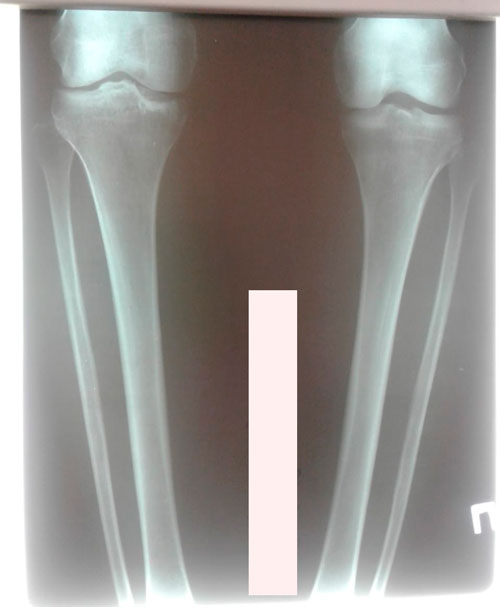

Исходник - 49 лет. Киргизия.

Дата операции - 12.04.2019г.